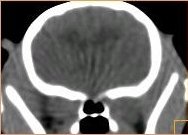

imágenes de TAC en el gato |